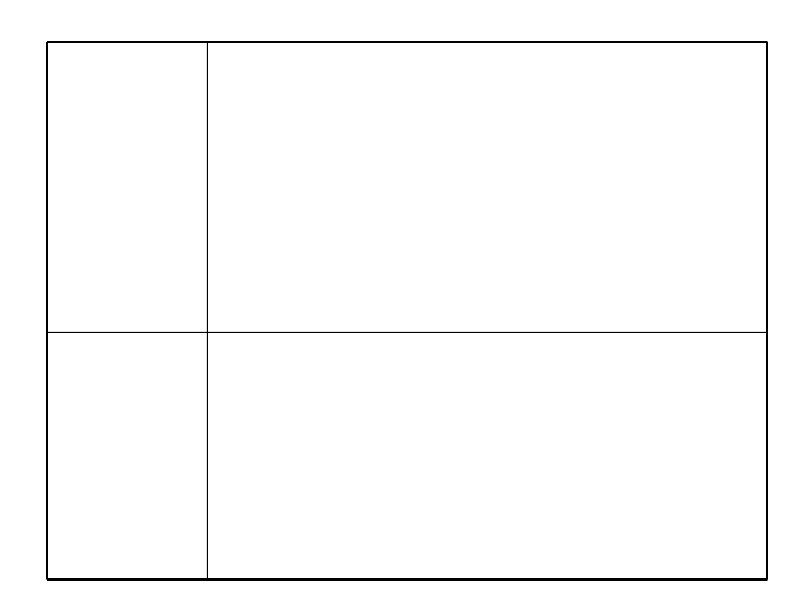

Схемы химиотерапии лимфогрануломатоза